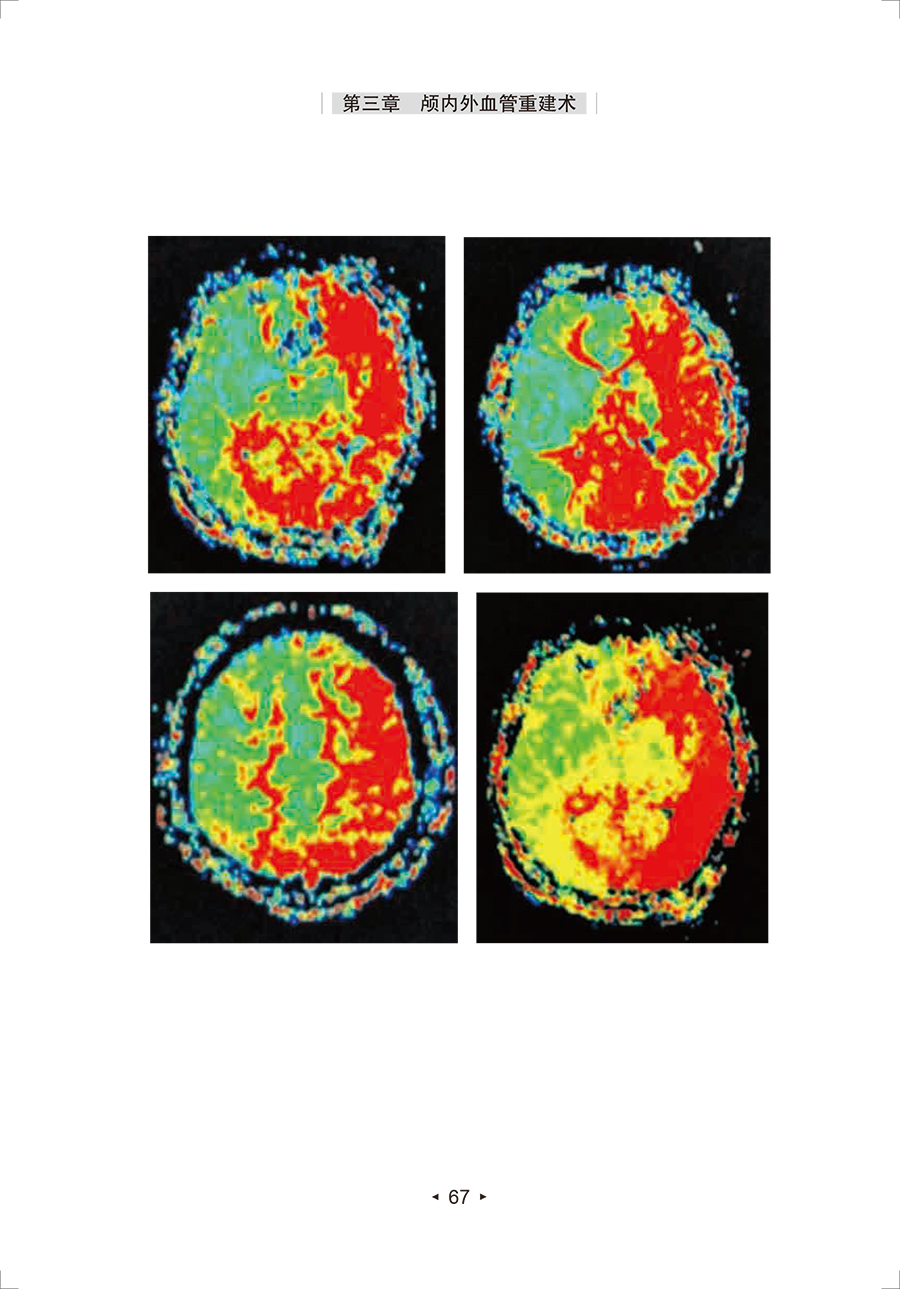

脑血管病是严重危害国人健康的重大疾病。外科治疗在脑卒中防治中扮演着重要角色。《脑卒中外科治疗》作为《脑卒中防治系列丛书》分册之一,由国家卫生健康委员会脑卒中筛查与防治工程委员会组织我国从事脑血管病外科治疗领域的知名专家悉心编撰而成。全书包括三大部分,分别阐述了缺血性脑血管病的外科干预、出血性脑血管病的外科干预和复合性手术技术。本书在前版的基础上,根据国内外新研究进展,并融合专家的临床实践经验,对第1版的内容进行了部分更新,并新增了脑血管重建技术在脑动脉瘤治疗中的应用及复合性手术技术在出血性和缺血性脑血管病治疗中的应用等内容,使本书的知识更新、体系更完整。每种手术治疗方法分别从适应证、禁忌证、手术要点、围手术期处理等方面进行了系统论述,图文并茂、实用性强。